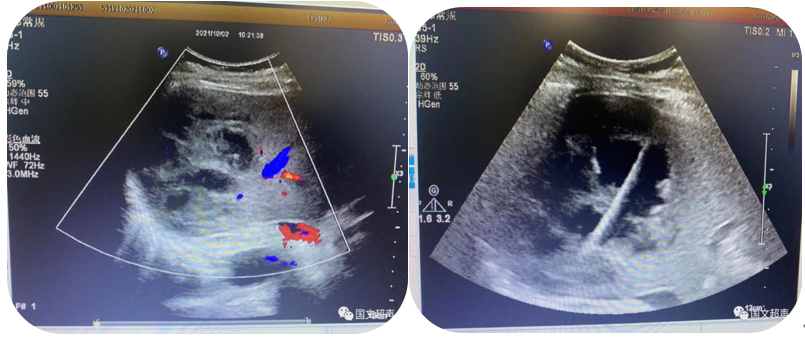

1.超聲引導(dǎo)下穿刺活檢

超聲的實(shí)時(shí)引導(dǎo)下,穿刺針插入腫大淋巴結(jié)、疑似占位等特定部位進(jìn)行組織抽吸、切割獲取病理標(biāo)本幫助疾病診斷。

超聲引導(dǎo)下淺表淋巴結(jié)穿刺活檢